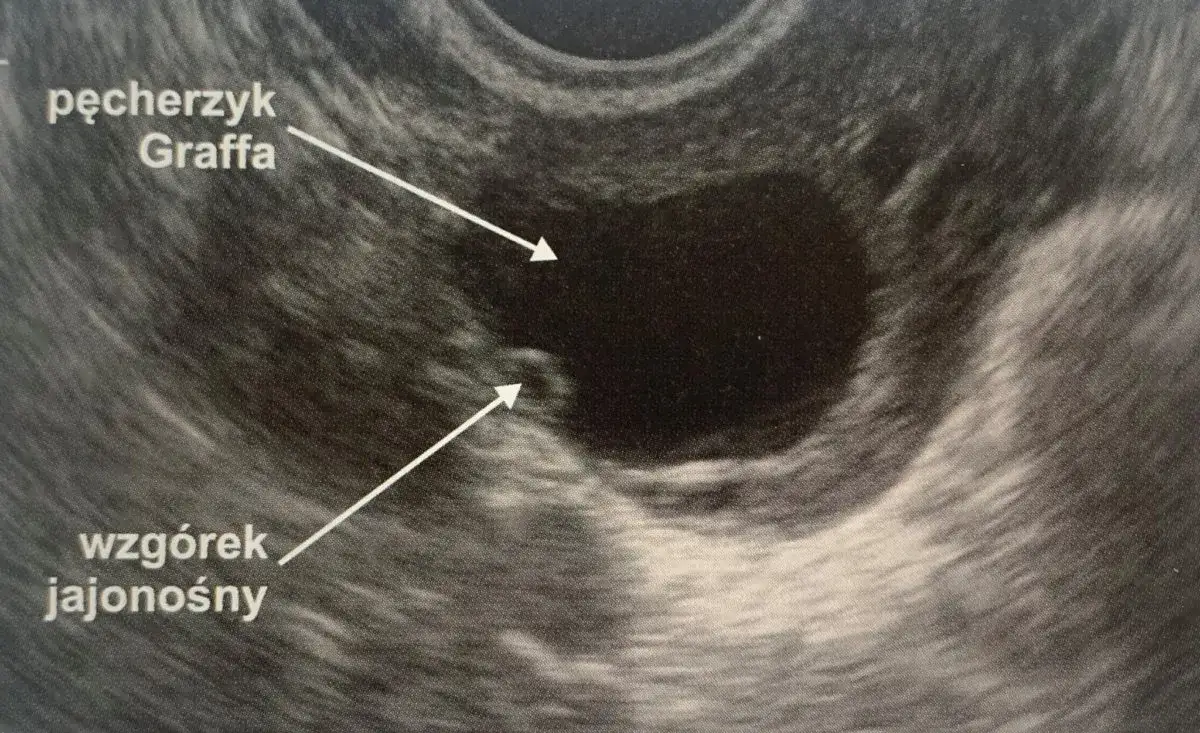

Pęcherzyk Graafa to niewielka struktura w jajniku, która zawiera niedojrzałą komórkę jajową. W każdym cyklu miesiączkowym, pod wpływem hormonów, jeden z pęcherzyków staje się "dominujący" i zaczyna intensywnie rosnąć. Jego główną rolą jest doprowadzenie komórki jajowej do pełnej dojrzałości, a następnie jej uwolnienie podczas owulacji. Kiedy badanie USG wykazuje pęcherzyk o wielkości 18 mm, jest to dla nas, lekarzy, bardzo ważna informacja. Oznacza to, że pęcherzyk jest już na zaawansowanym etapie dojrzewania i zbliża się do optymalnej wielkości do pęknięcia, która zazwyczaj mieści się w zakresie 18-26 mm.

Pęcherzyk 18 mm jest już dojrzały, ale nie oznacza to, że pęknie natychmiast. Uważa się, że pęcherzyk jest dojrzały i gotowy do pęknięcia, gdy osiąga wielkość od 18 do 26 mm. Z mojego doświadczenia wynika, że wielu specjalistów przyjmuje, że pęcherzyk pęka najczęściej przy wielkości 20-24 mm. To daje nam pewien zakres, a dokładny moment zależy od indywidualnych predyspozycji i sygnałów hormonalnych.

Obraz USG po owulacji: czego szuka lekarz?

Po owulacji, podczas kolejnego badania USG, lekarz szuka konkretnych zmian, które potwierdzą, że pęcherzyk pękł i komórka jajowa została uwolniona. Przede wszystkim nie będzie już widocznego dominującego pęcherzyka. W jego miejscu pojawi się inna struktura, a także mogą być widoczne inne charakterystyczne cechy.

Ciałko żółte i płyn w zatoce Douglasa jako dowody na pęknięcie pęcherzyka